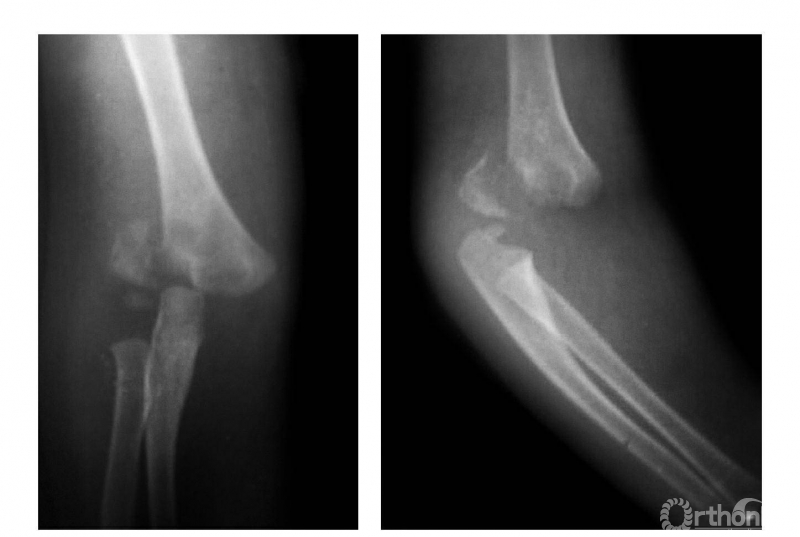

三、伸展型

例:肱骨下端骨骺分离伴前臂向后侧移位(图3)。

图3

四、屈曲型

例:肱骨下端骨骺分离伴前臂向前移位(图4)。

图4